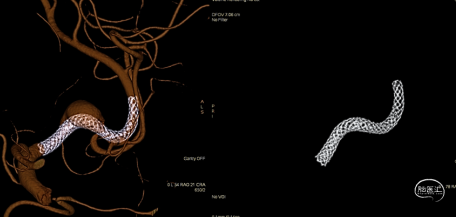

术中Dyna-CT可见支架打开充分且贴壁良好。

支架远端释放10mm,确认支架打开后整体回撤至计划铆钉点 利用推拉技术让支架在载瘤动脉内充分打开

最后支架尾端减张释放,减影像及Dyna-CT可见支架完全打开且贴壁良好